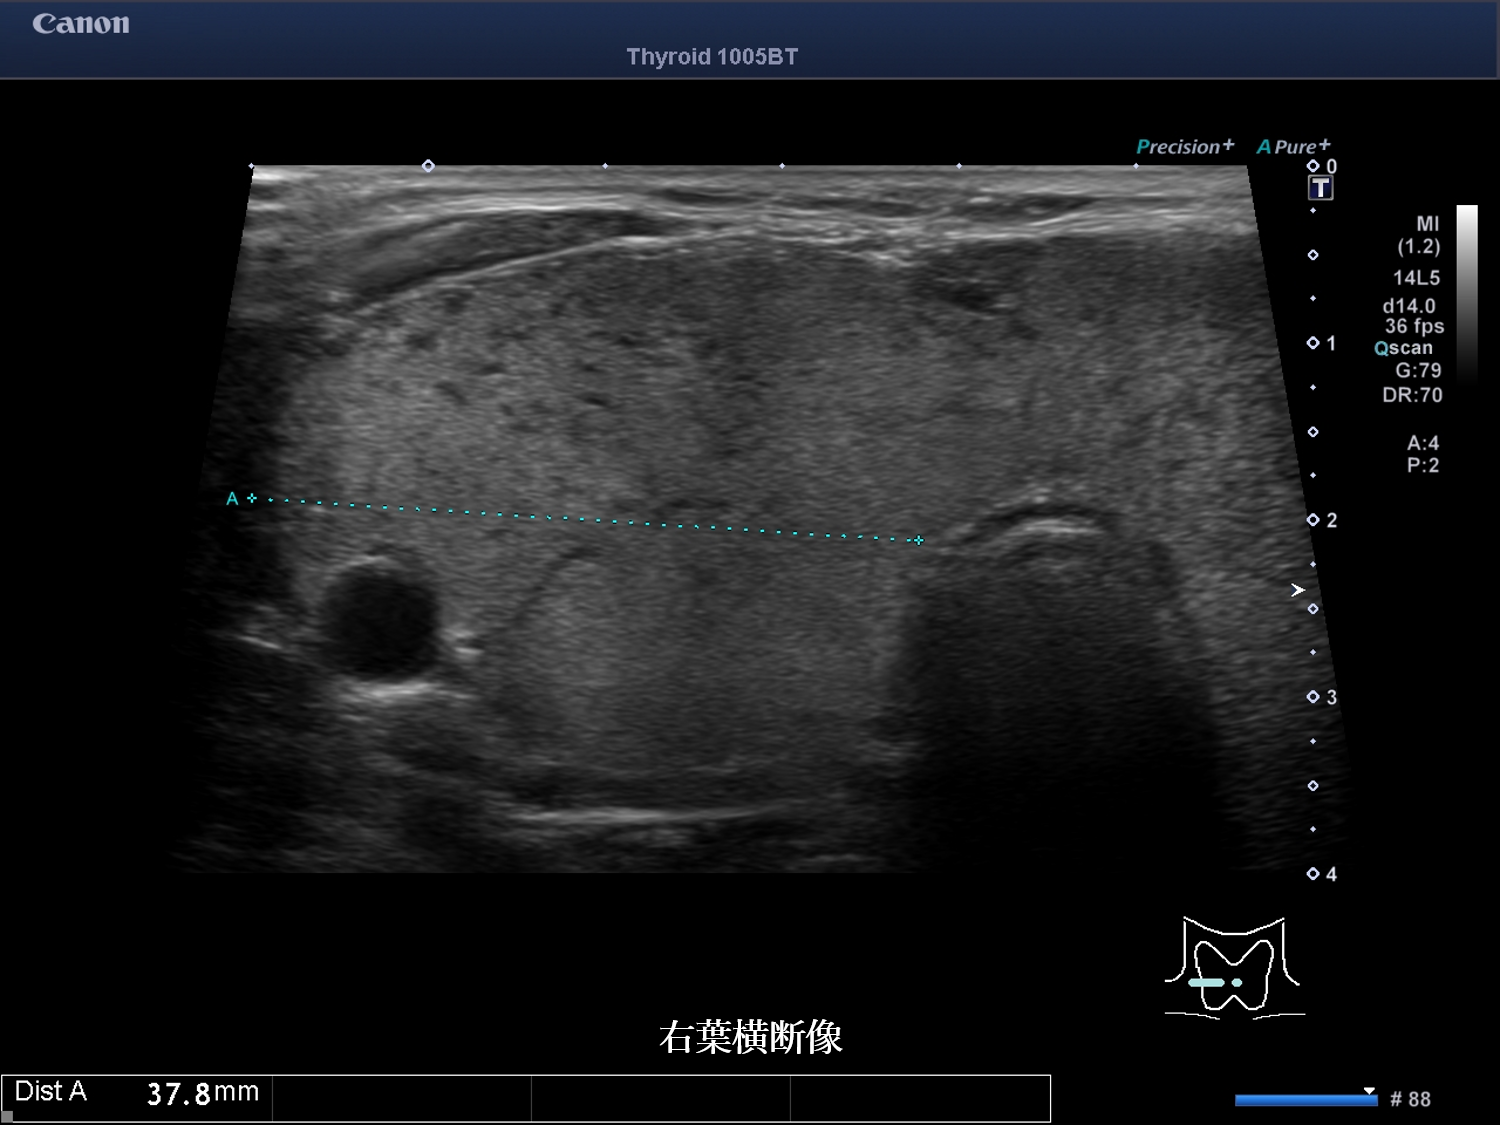

甲状腺超音波画像 画像1(No20-21_1)画像2(No20-21_2)画像3(No20-21_3)

① 結節性病変は認めない

② びまん性に腫大している

③ 内部エコーは不均質である

⑤ 低エコー域内の血流低下を認める